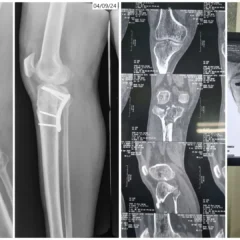

Regular follow-ups were conducted to monitor fracture healing and maintain alignment.

With stable fixation and dedicated physiotherapy, Mrs. Ananthamma achieved:

Good fracture alignment

Stable bone healing

Progressive return to weight-bearing

Improved knee mobility